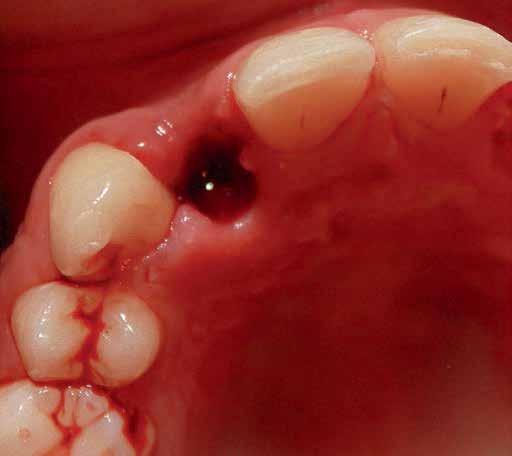

Directly after immediate implant placement, a customized healing abutment was fabricated using Cervico kit. The selection was made intraorally using a special handle to place the indicator over the restorable area. (fig 6) Utilize the anatomical shape tab from the same group as per the anterior tooth missing. The anterior suitable stock healing abutment was directly screwed on the implant analog and was fixed at the corresponding well of the silicone mold, and the custom healing abutment was fabricated with nano‐hybrid flowable resin (3M™ Filtek™ Supreme Flowable Composite) (Fig 7,8). Minor selective grinding, finishing, and polishing were made when necessary to achieve a smooth, lustrous tissue contact surface, and screwed to the implant. 15 (Fig 9)

The prosthetic procedures for definitive restorations were performed 3 months after implant placement. The healing abutment was removed (Fig 10) scan body was placed in position and a digital implant-level impression was made using an intraoral scanner (Medit I 700 3D scanners) (16) (Fig 11,12)